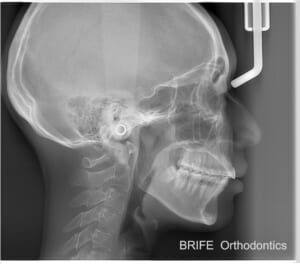

もう一種類が頭部X線規格写真です。セファログラムとも言います。これは顔を真横(または真正面)から撮影することで、顎のサイズを計測したり、前歯の角度を計測するなどの分析を行います。

セファログラム